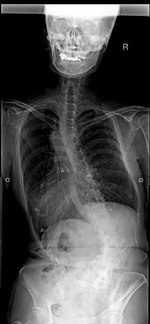

せぼね(脊椎)は7個の頚椎、12個の胸椎、5個の腰椎と仙椎から構成されます。正常な状態では脊椎は正面から見ると真っ直ぐです。一方側弯症では正面から見た時に椎体がねじれ(回旋)を伴いながら、脊椎が左右に曲がっている状態です。

せぼね全体のバランスや変形の進行を見るために数ヶ月おきに立位でのX線検査やCT検査、MRI検査を行います。進行例では脊髄の圧迫をより詳しく評価するために、入院して脊髄造影検査を行う場合があります。さらに、同時にどの神経が痛みの原因となっているかを明らかにするため、神経の枝に直接麻酔薬を注入する選択的神経根ブロックを行う場合があります。また骨密度が低いと側弯症が進行する可能性があるため、骨密度検査を行う場合があります。